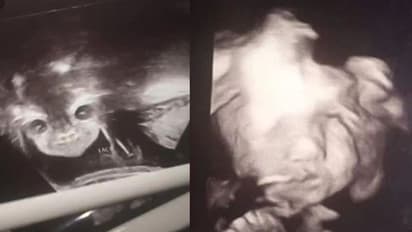

അയന്ന കാരിംഗ്ടൺ എന്ന 17കാരി സ്കാൻ ചെയ്യുന്നതിനിടെ കുഞ്ഞിന്റെ മുഖമൊന്ന് കാണാൻ സ്ക്രീനിലേക്ക് നോക്കി. അയന്ന ശരിക്കുമൊന്ന് ഞെട്ടിപ്പോയി. വയറ്റിൽ കിടക്കുന്ന കുഞ്ഞിന്റെ മുഖം പിശാചിന്റെത് പോലെയിരിക്കുന്നുവെന്ന് അയന്നയ്ക്ക് തോന്നി. 24ാം ആഴ്ച്ചത്തെ സ്കാൻ ചെയ്യുന്നതിനിടെയാണ് അതിശയിപ്പിക്കുന്ന ഈ കാഴ്ച് കാണാനായത്.

ഉടൻ തന്നെ ഡോക്ടർ വയറ്റിന് മുകളിൽ ഡോപ്ലർ വയ്ക്കുകയും ആ നിമിഷം കുഞ്ഞ് ചിരിക്കുന്ന മുഖം കാണാനായെന്ന് അയന്ന പറയുന്നു. സ്കാൻ കോപ്പിയുടെ ഫോട്ടോകൾ അയന്ന ഫേസ്ബുക്കിൽ ഷെയർ ചെയ്യുകയായിരുന്നു. യുഎസിലാണ് സംഭവം. കുഞ്ഞ് വയറ്റിൽ കിടന്ന് കാണിക്കുന്ന വികൃതികൾ സന്തോഷത്തോടെ ആസ്വാദിക്കുകയാണെന്ന് അയന്ന പറഞ്ഞു.